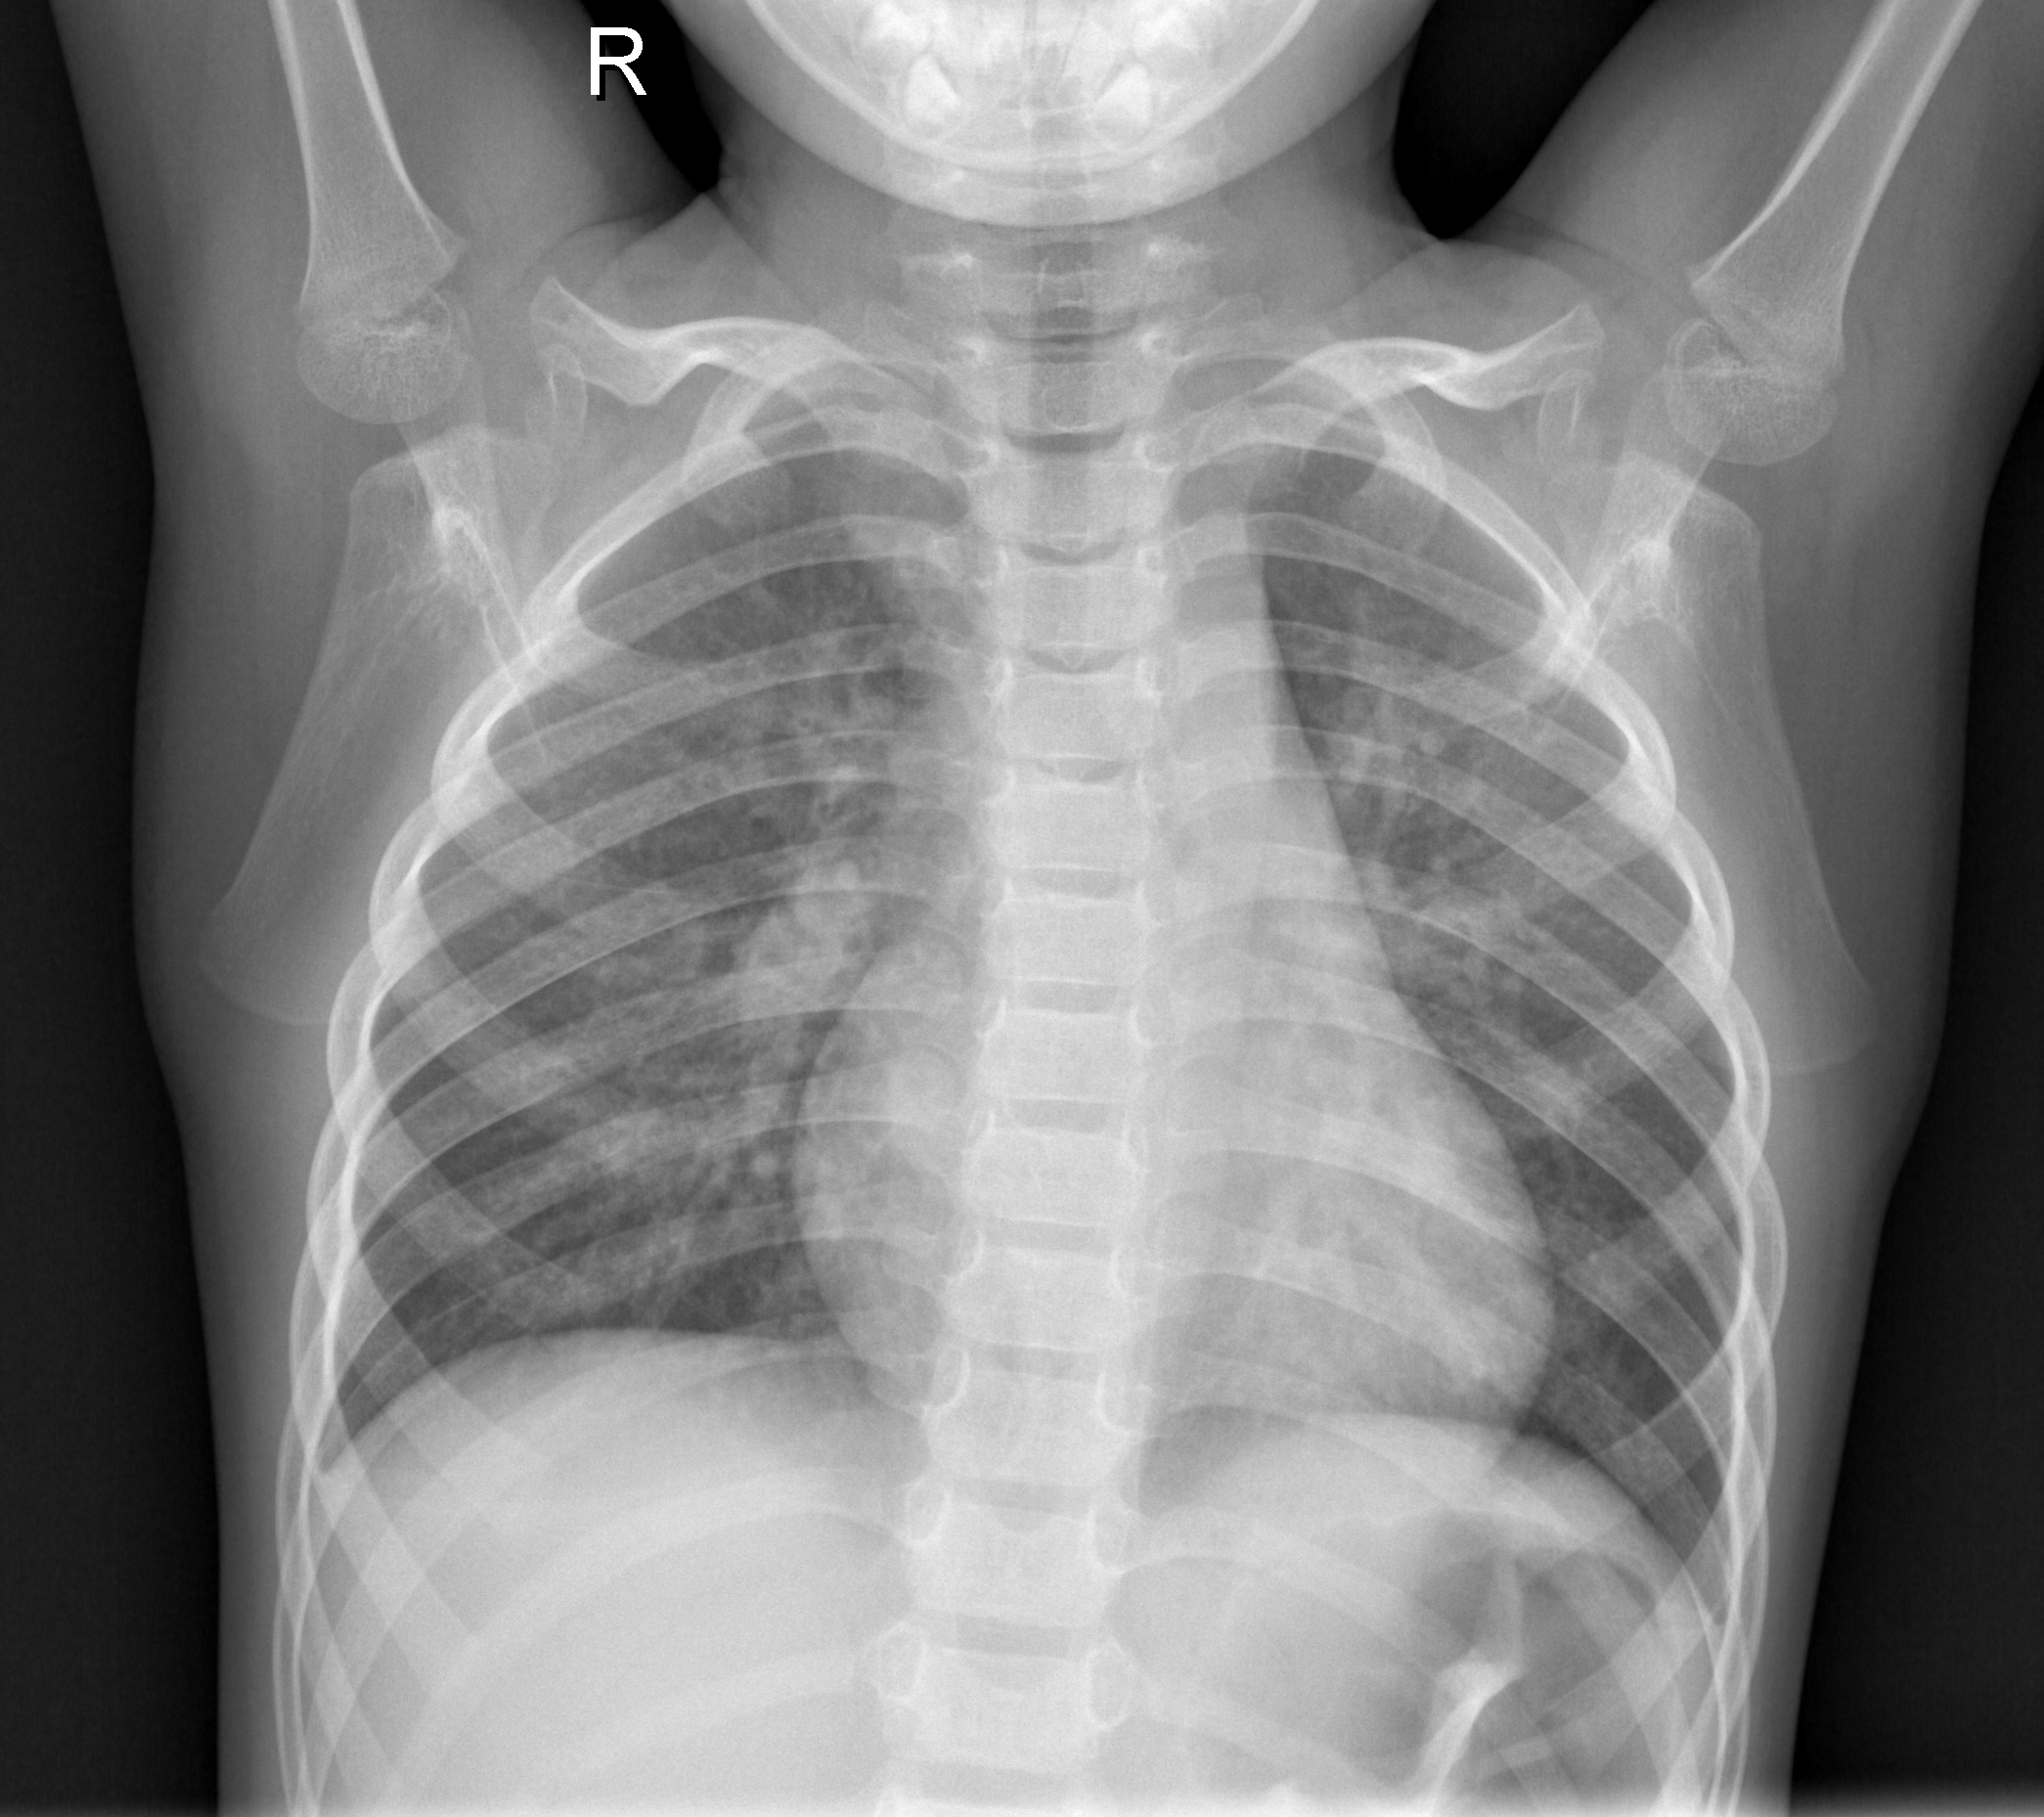

Another drawback for the early diagnosis of pneumonia is the human-dependent detection. Expert radiologists need to have sufficiently trained eyes in order to be able to differentiate between the heterogeneous color distribution of air while flowing in the lungs. This may be seen in different colors on the x-ray image taken, yet not be the dense pneumonia fluid. Thus, it’s highly significant for a radiologist to be able to tell whether if the white spots on the x-ray film actually correspond to the fluid itself. As a result of the error margin of the human eye, there are many cases where the radiologists fail to make the correct diagnosis. In both cases, whether if it’s a false positive or false negative diagnosis, it has substantial impacts on the human body. Therefore, computational methods in the diagnosis step of the disease are reliable in terms of consistency. In fig 1, different images with and without pneumonia can be seen ([2]). The imperceptibility of the healthy versus the pneumonia images can also be witnessed, which portrays the need of well-trained eyes in order to be able to differentiate.

Refer to caption

Figure 1: X-ray Images with and without Pneumonia